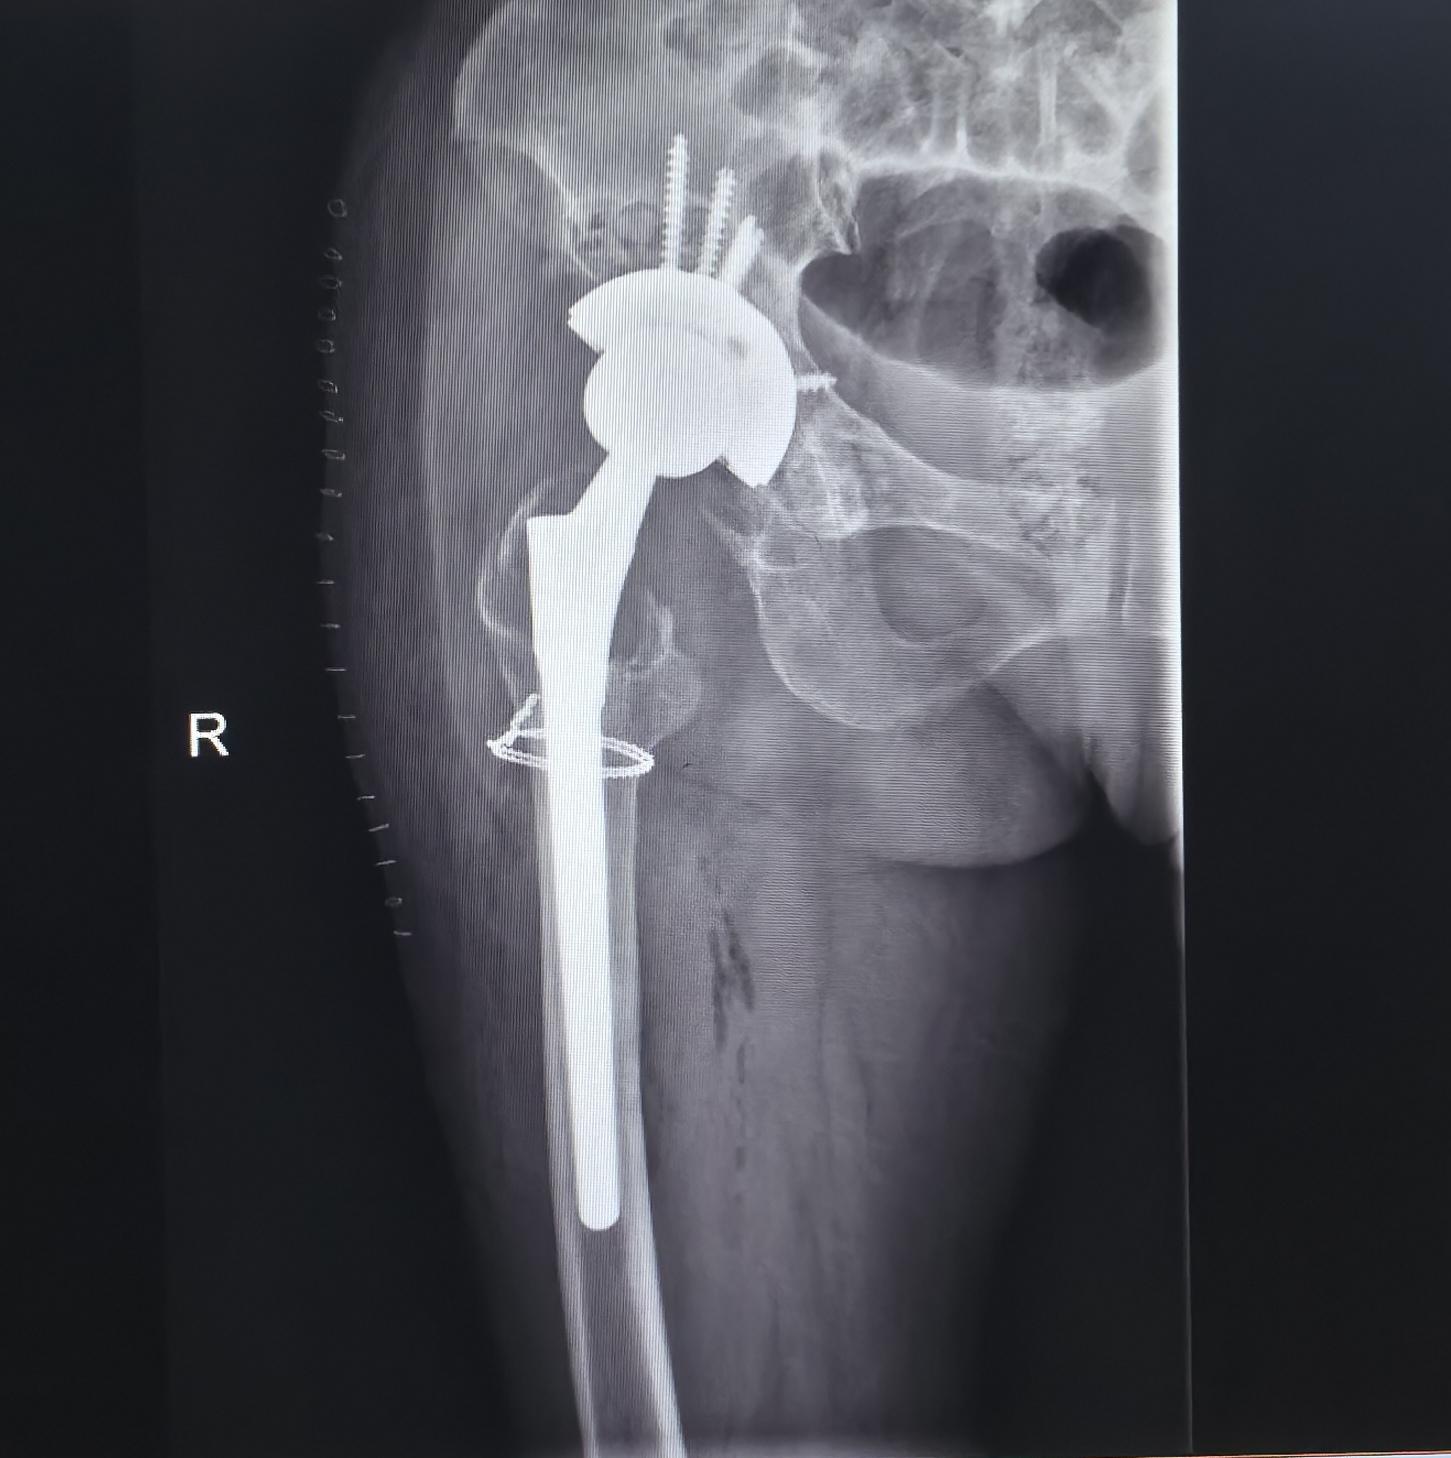

全髋关节翻修术。82岁老太太,THA后(14年)假体松动、骨溶解,全髋翻修,再续20年🌹